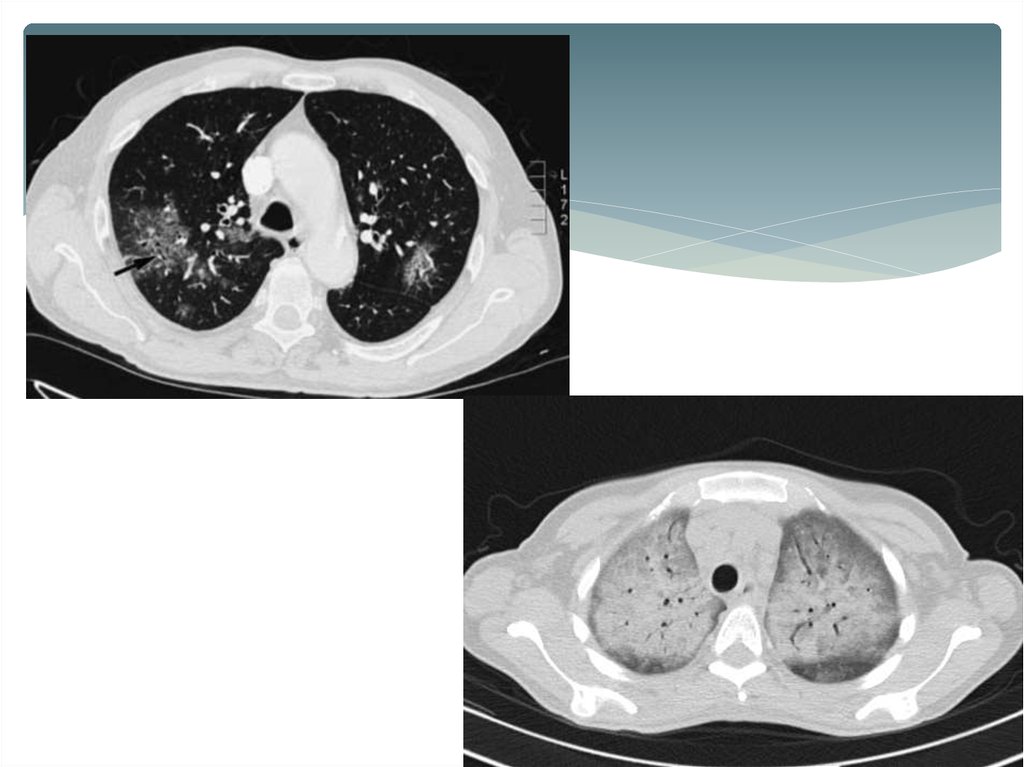

10. Диагностика